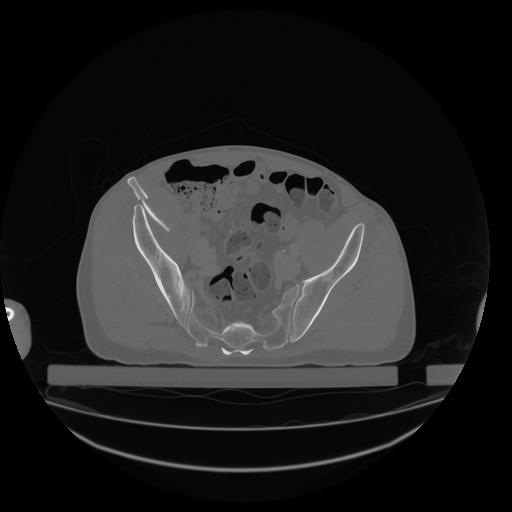

34 CUERPO,CE,Vol,1.0,CUERPO,,